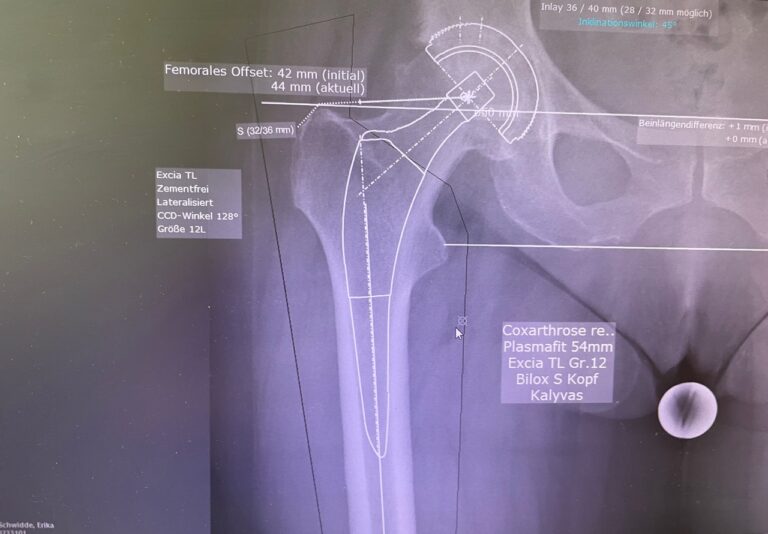

Πώς πραγματοποιείται η επέμβαση

Κατά τη διάρκεια της ολικής αρθροπλαστικής ισχίου:

- αφαιρείται η κατεστραμμένη μηριαία κεφαλή

- τοποθετείται μηριαίο στέλεχος εντός του μηριαίου οστού

- αντικαθίσταται η κοτύλη με τεχνητό κυπέλλιο

- εφαρμόζεται νέα αρθρική επιφάνεια για ομαλή και ανώδυνη κίνηση

Τύποι προθέσεων & χειρουργική τεχνική

Οι προθέσεις μπορεί να είναι:

- τσιμεντούμενες

- χωρίς τσιμέντο

- υβριδικές

Η επιλογή γίνεται εξατομικευμένα, λαμβάνοντας υπόψη:

- την ηλικία του ασθενούς

- την ποιότητα του οστού

- το επίπεδο δραστηριότητας

- τα συνοδά νοσήματα

Ο ακριβής προεγχειρητικός σχεδιασμός μειώνει σημαντικά τον κίνδυνο επιπλοκών